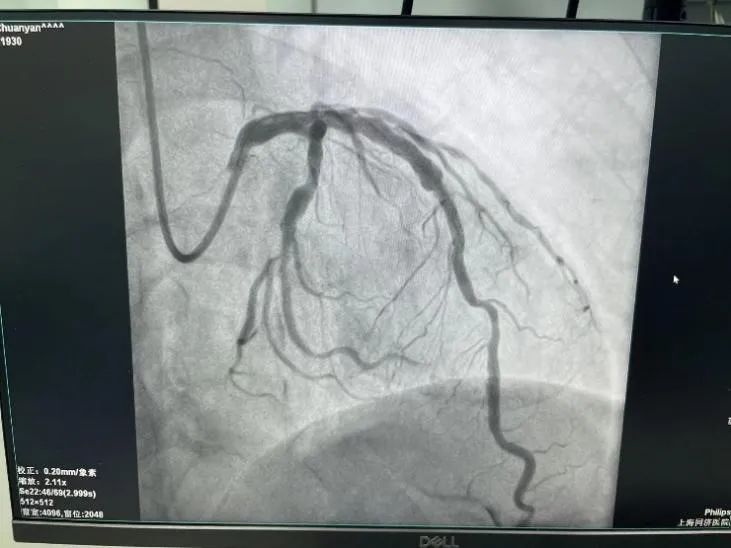

此次手术由心血管内科主任刘学波教授、来晏主任医师和叶梓医师共同参加。在冲击波球囊发放了10次脉冲后,医生们通过腔内影像看到原来厚厚的钙化层出现了明显的裂隙,血管轻易的就被扩张开了,后续的支架植入也非常的顺利。冲击波球囊是冠脉介入治疗对付钙化病变的又一大利器,一定能够给更多的患者带来福音。

支架植入后